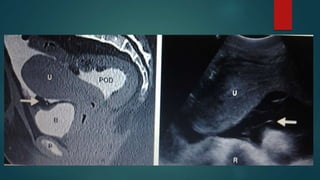

Pelvic peritoneal spaces

 The most dependent portion of the

peritoneal spaces in supine & erect

positions is in the pelvis

 In males the rectovesical space

lies between the anterior

mesorectal fascia & post wall of the

bladder

 In females the retrouterine space

(pouch of douglas) lies betwn

uterine wall & ant mesorectal fascia